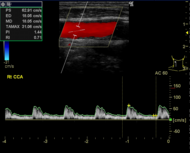

脳ドックで評価できるのは、無症候性脳梗塞(かくれ脳梗塞)、未破裂脳動脈瘤、脳腫瘍、そして認知症です。MRIやエコーに加えて、血液検査、心電図、神経学的診察では、動脈硬化や脳卒中を起こしうる不整脈(心房細動)、パーキンソン病や本態性振戦の有無が評価できます。

頸動脈エコー検査

頸動脈エコー検査(エコー検査は省略可です)